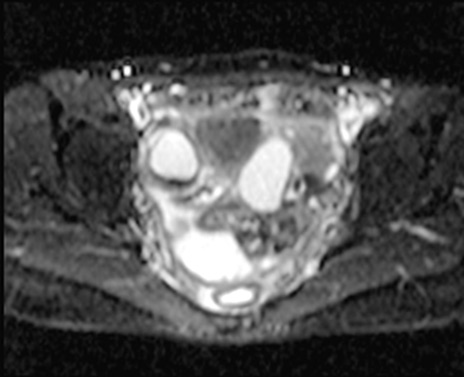

MRI(4日後)